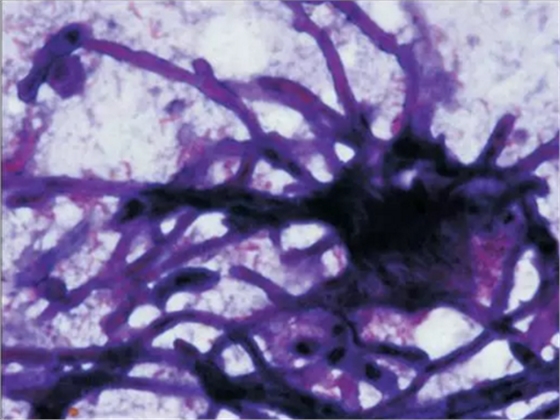

初步診斷為口腔毛霉菌病。取部分軟腭組織做病理學(xué)檢查。病理檢查顯示組織中含有大量無(wú)包膜的真菌、壞死血管組織,結(jié)果支持毛霉菌病的診斷。